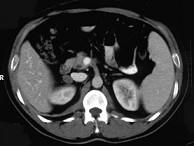

问题 女,23岁,满月脸、向心性肥胖,CT扫描如图所示,应诊断为()

选项 A.右侧肾上腺增生 B.右侧肾上腺腺瘤 C.右侧肾上腺腺癌 D.右侧肾上腺嗜铬细胞瘤 E.右侧肾上腺转移瘤

答案 B